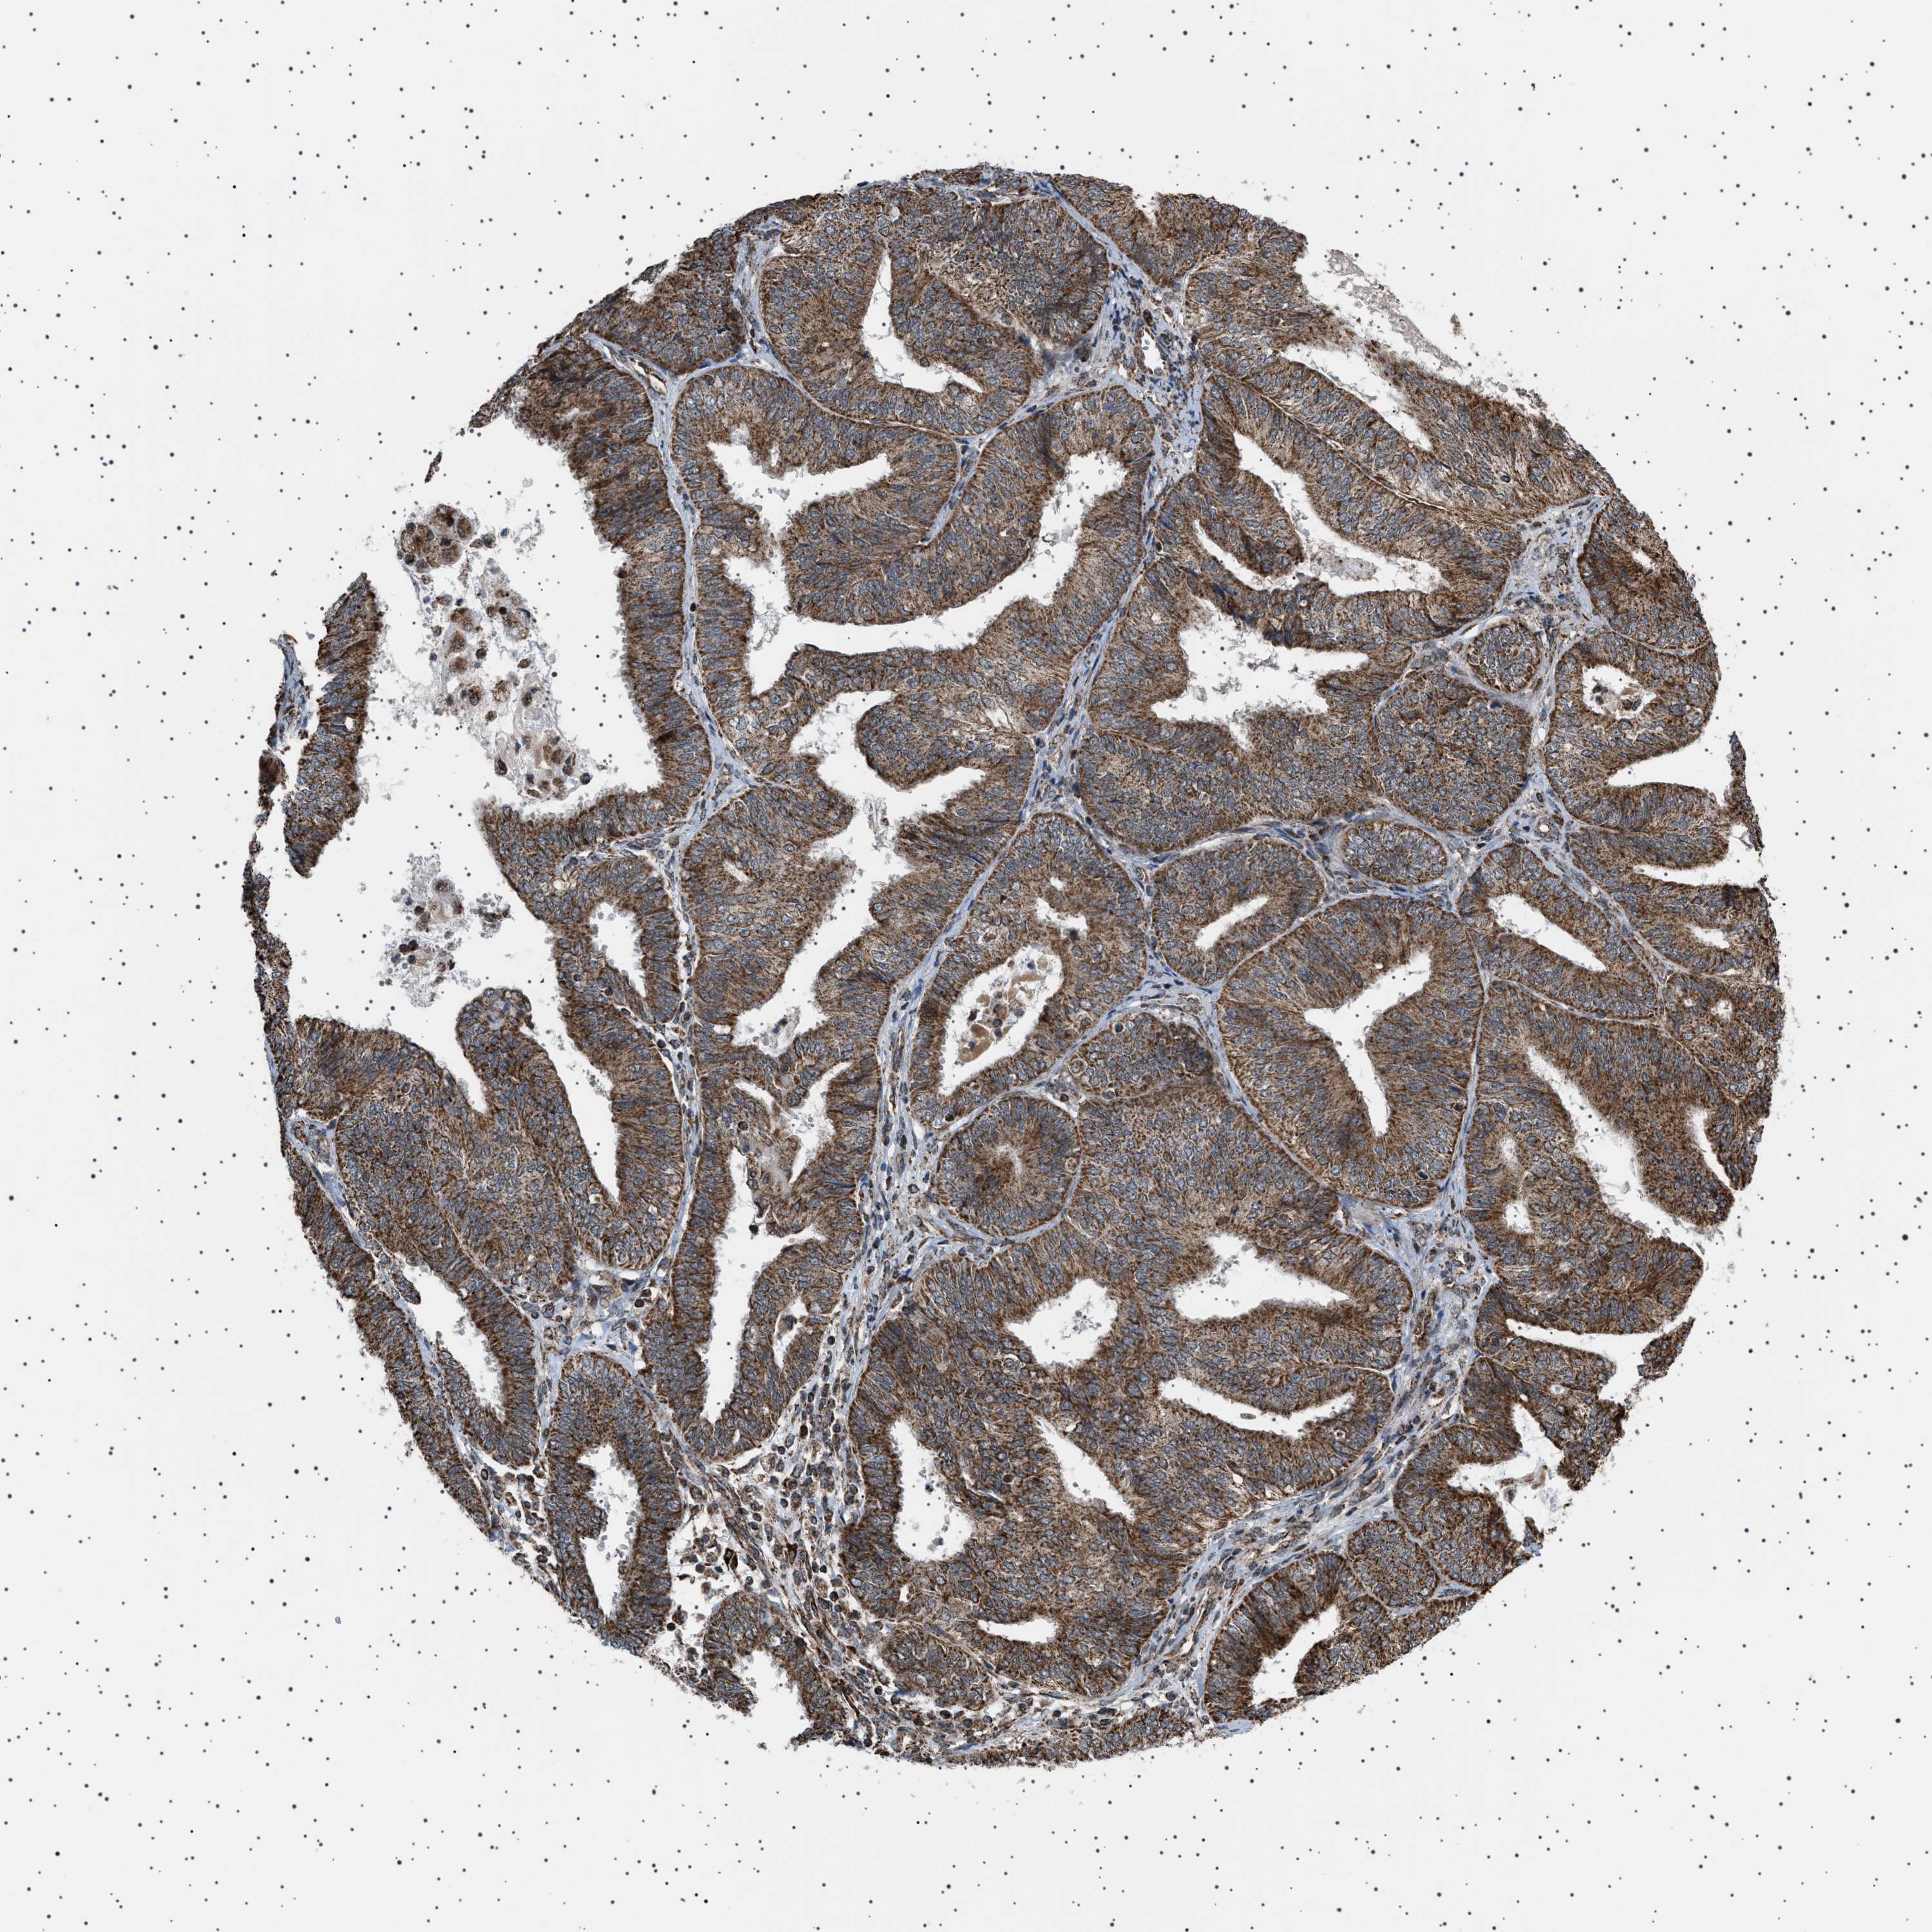

ENDOMETRIAL CANCER - Protein expressioni

A mouse-over function shows sample information and annotation data. Click on an image to view it in a full screen mode. Samples can be filtered based on level of antibody staining by selecting one or several of the following categories: high, medium, low and not detected. The assay and annotation is described here.

Note that samples used for immunohistochemistry by the Human Protein Atlas do not correspond to samples in the TCGA dataset.

Antibody stainingi

Antibody staining in the annotated cell types in the current human tissue is reported as not detected, low, medium, or high, based on conventional immunohistochemistry profiling in selected tissues. This score is based on the combination of the staining intensity and fraction of stained cells.

Each image is clickable and will lead to virtual microscopy that enables deeper exploration of all samples and also displays staining intensity scores, fraction scores and subcellular localization as well as patient and tissue information for each sample.

Antibody HPA017214

Staining

High

Medium

Low

Not detected

Intensity

Strong

Moderate

Weak

Negative

Quantity

>75%

75%-25%

<25%

None

Location

Nuclear

Cytoplasmic/membranous

Cytoplasmic/membranous,nuclear

Adenocarcinoma, NOS